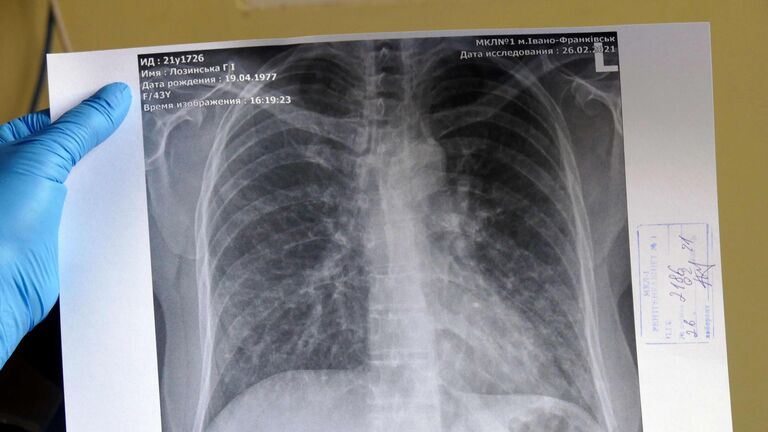

Рентгеновские снимки при пневмоцистной пневмонии